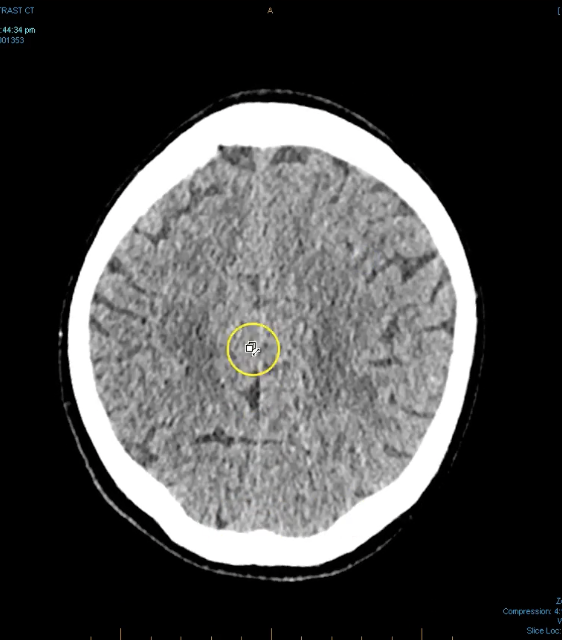

term image

lateral ventricles